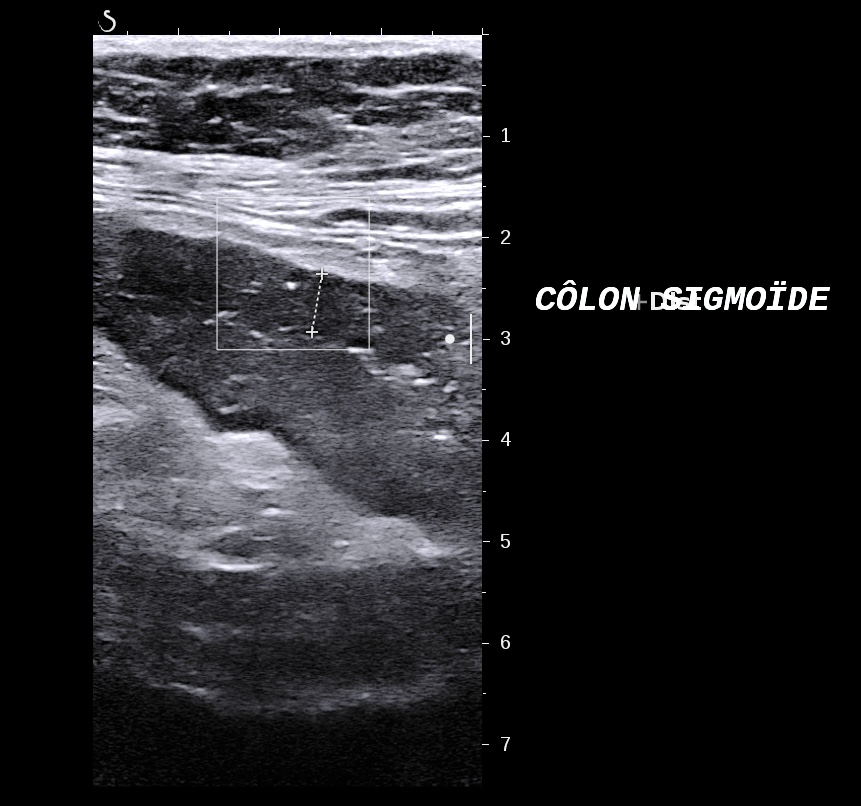

Sur un sigmoide dans une forme récente, la muqueuse est plus épaisse, on a parfois un faux aspect d'irrégularité, mais la structure en couches est conservée

L'épaississement prédomine à la 3 ième couche hyperéchogène( > 1/3 de la paroi), il est continue, régulier, cironférentiel

La structure en couche est conservée

La graisse est peu infiltrée, l'activité doppler modérée.